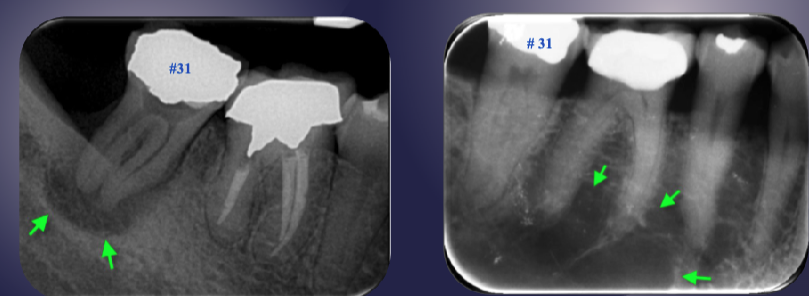

differentiate the pathology of the 2 images

left: loss of apical lamina dura + periapical radiolucency

right: normal lamina dura + radiolucency due to submandibular fossa

left: widened PDL + periapical radiopaque area + non-vital tooth → sclerosing osteitis

right: normal PDL + periapical radiopaque area due to dense bone island + vital tooth → normal